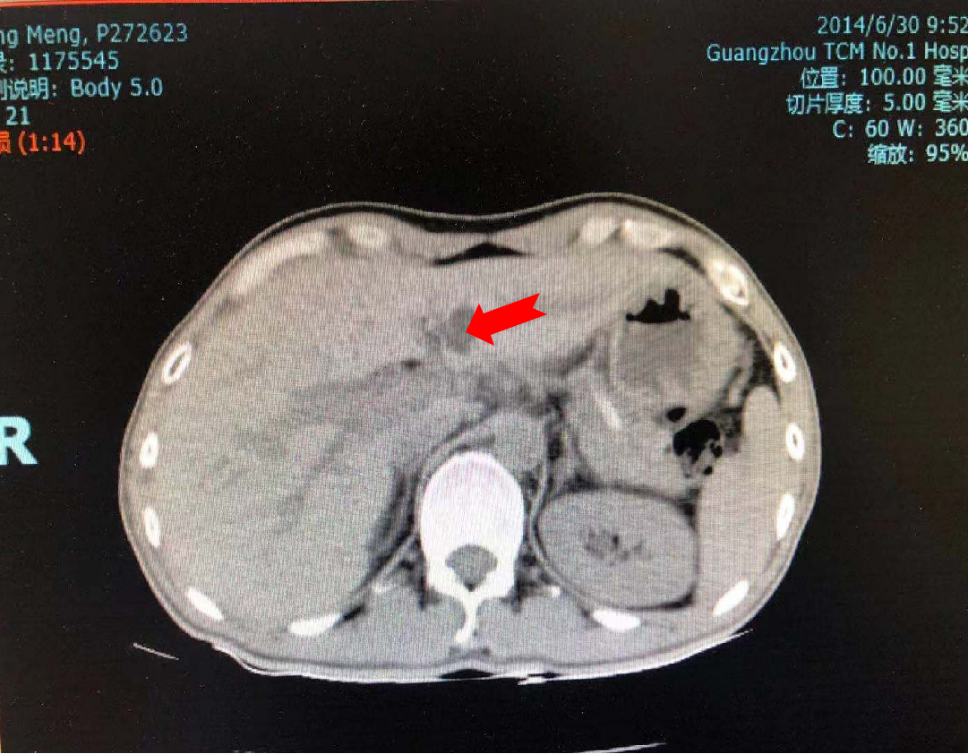

1、患者十二指肠壶腹Ca根治术后6年余,未见肿瘤复发。

治疗前:2014年6月30日CT示:十二指肠壶腹Ca根治术后,胆囊及胰头切除,胰管内支架,胃空肠吻合,局部腹腔多发小淋巴结肿,多发肝囊肿,右肾囊肿,余未见明显异常。